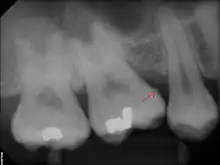

Calculus deposit (indicated with a red arrow) on x-ray image